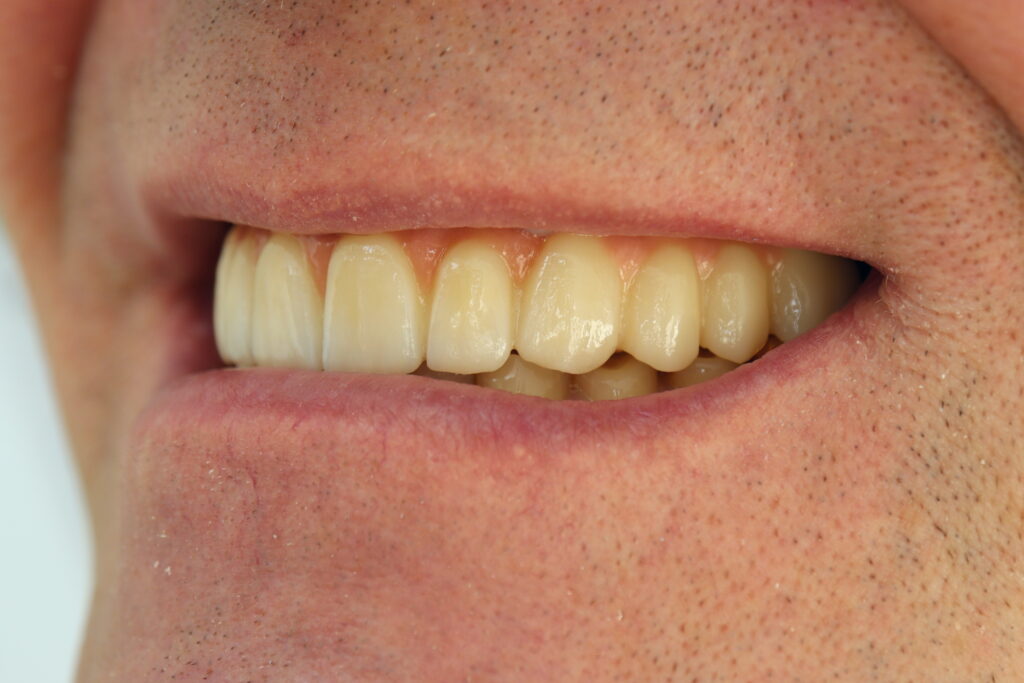

Спустя 27 дней был зафиксирован протез с опопрой на дентальные имплантаты из диоксида циркония с каркасом из титана.

Результат

Пациенту были установлены 6 имплантатов Megagen AnyOne по системе All-on-6 на верхней челюсти и 4 имплантата на нижней по классической двухэтапной методике.